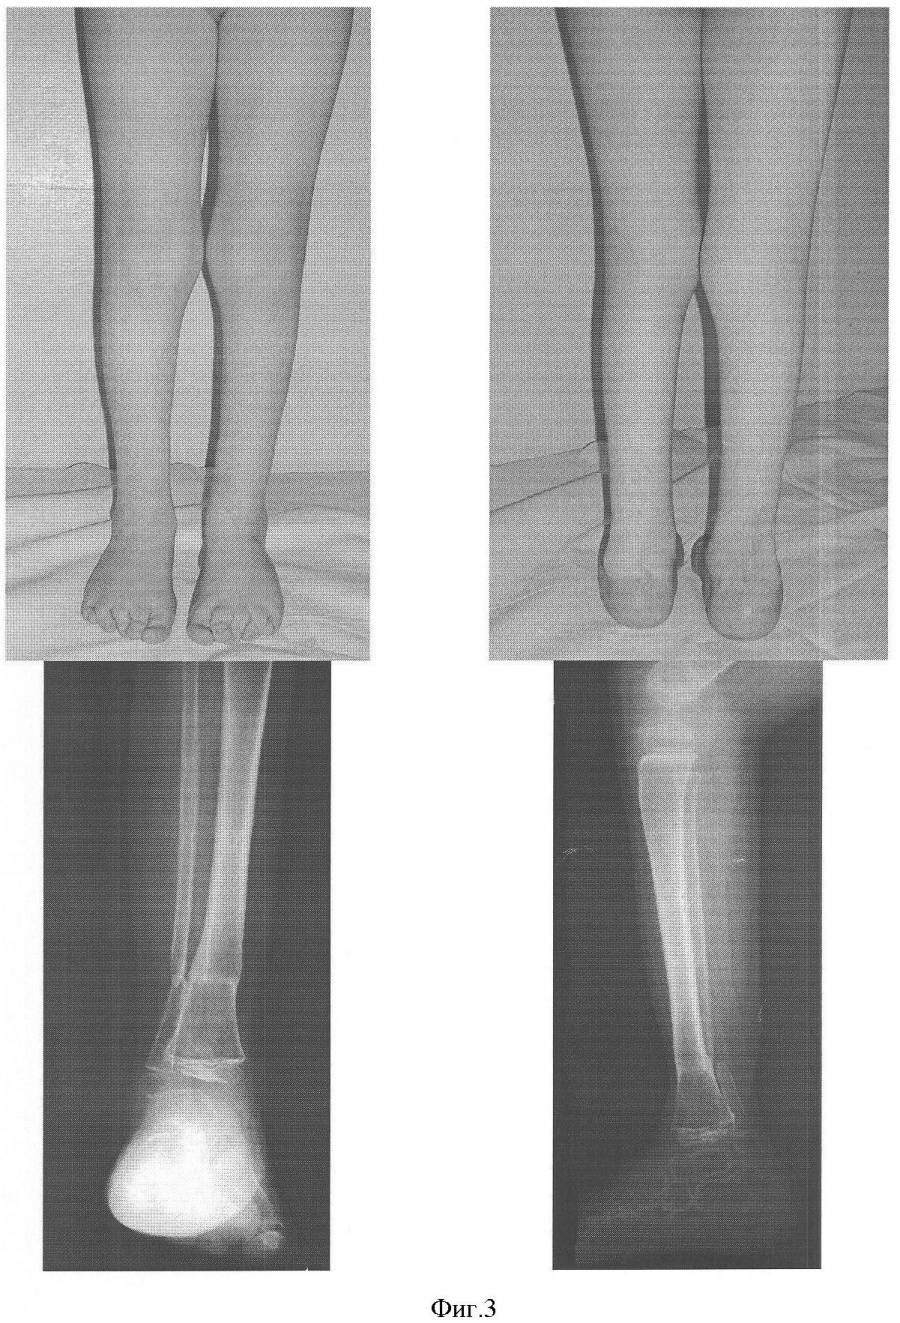

На фиг.1 представлены фото и рентгенограмма конечности ребенка 3 лет до оперативного лечения.

На фиг.3 – фото и рентгенограммы конечности ребенка 3 лет после оперативного лечения.